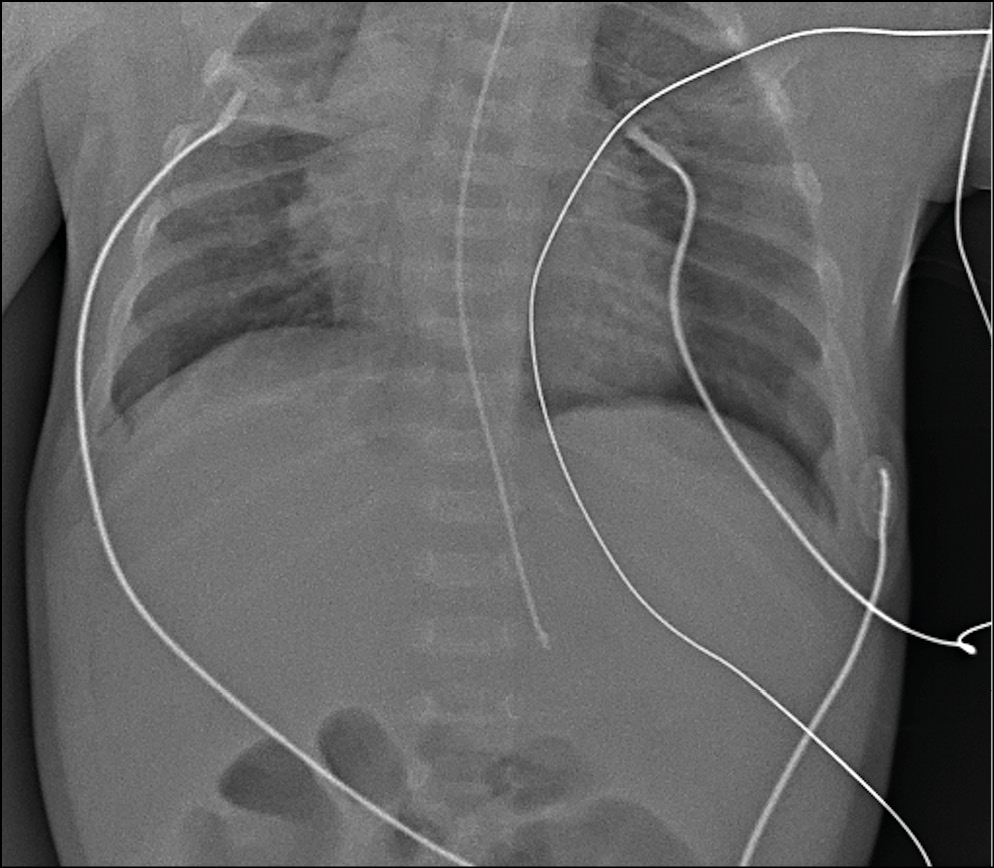

При невозможности вертикализации пациента для диагностики наличия свободного газа в брюшной полости возможно выполнение исследования в боковой проекции в положении лежа на спине (рис. 6).

Рис. 6. Рентгенограмма органов брюшной полости в боковой проекции. Исследование выполнено при помощи микрофокусного рентгеновского аппарата.

Fig. 6. Abdomens radiograph in lateral view. Microfocus X-ray device.